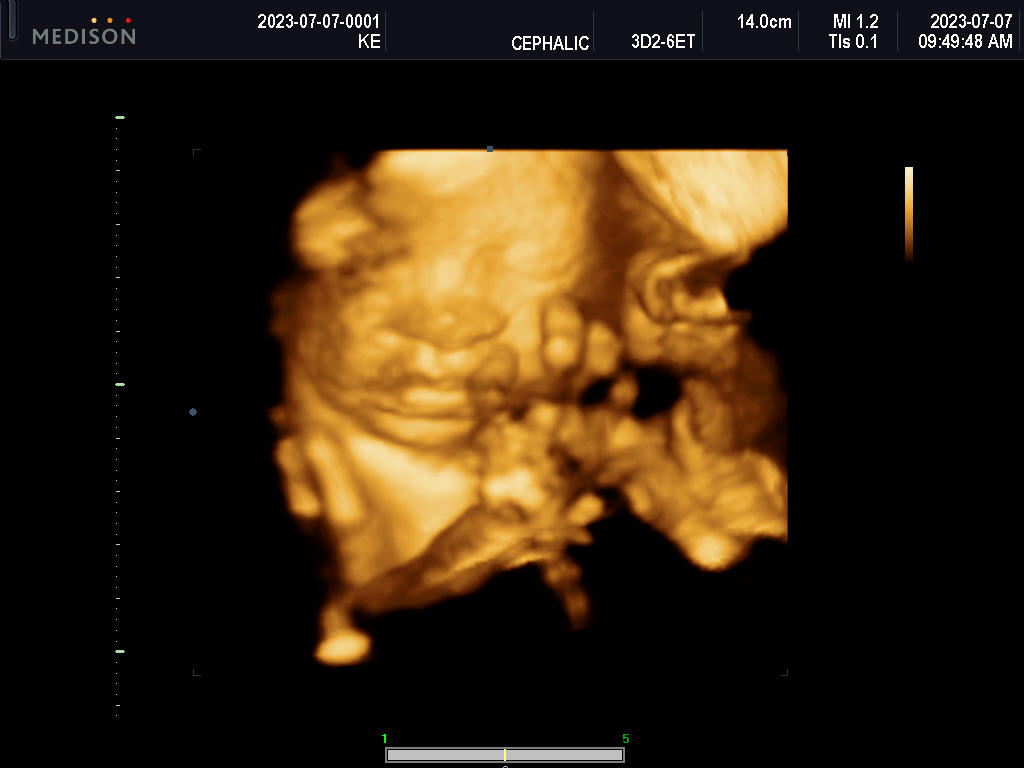

What will she look like?

What parts of us will she carry?

Will she have Nono’s forhead? FIFI’s stubbornness?